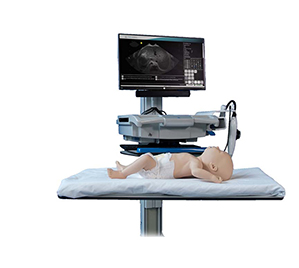

Intelligent Ultrasound is unlocking ultrasound for everyone by training clinicians in the classroom, and then supporting and guiding them in the clinic, with real-time AI based image analysis software.

Intelligent Ultrasound is unlocking ultrasound for everyone by training clinicians in the classroom, and then supporting and guiding them in the clinic, with real-time AI based image analysis software.

Intelligent Ultrasound vision is to harness the power of the new generation of AI algorithms to make ultrasound simpler to use and easier to learn by providing guidance and support to medical professionals whilst they are scanning..